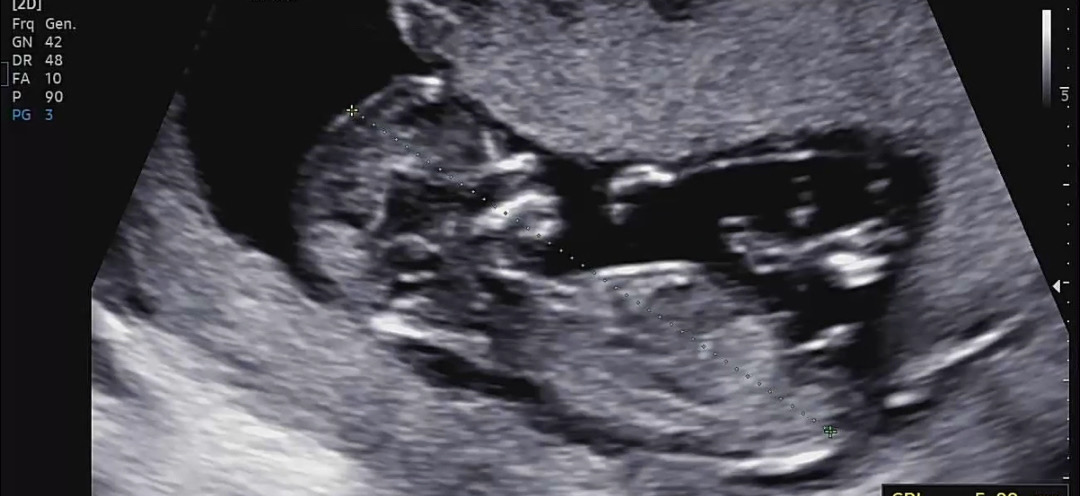

챗지피티도 헷갈리는 12주차 각도법 어떻게 보이실까용??!!

챗지피티는 딸같다하는데 제눈엔 아들같기두해서요!!